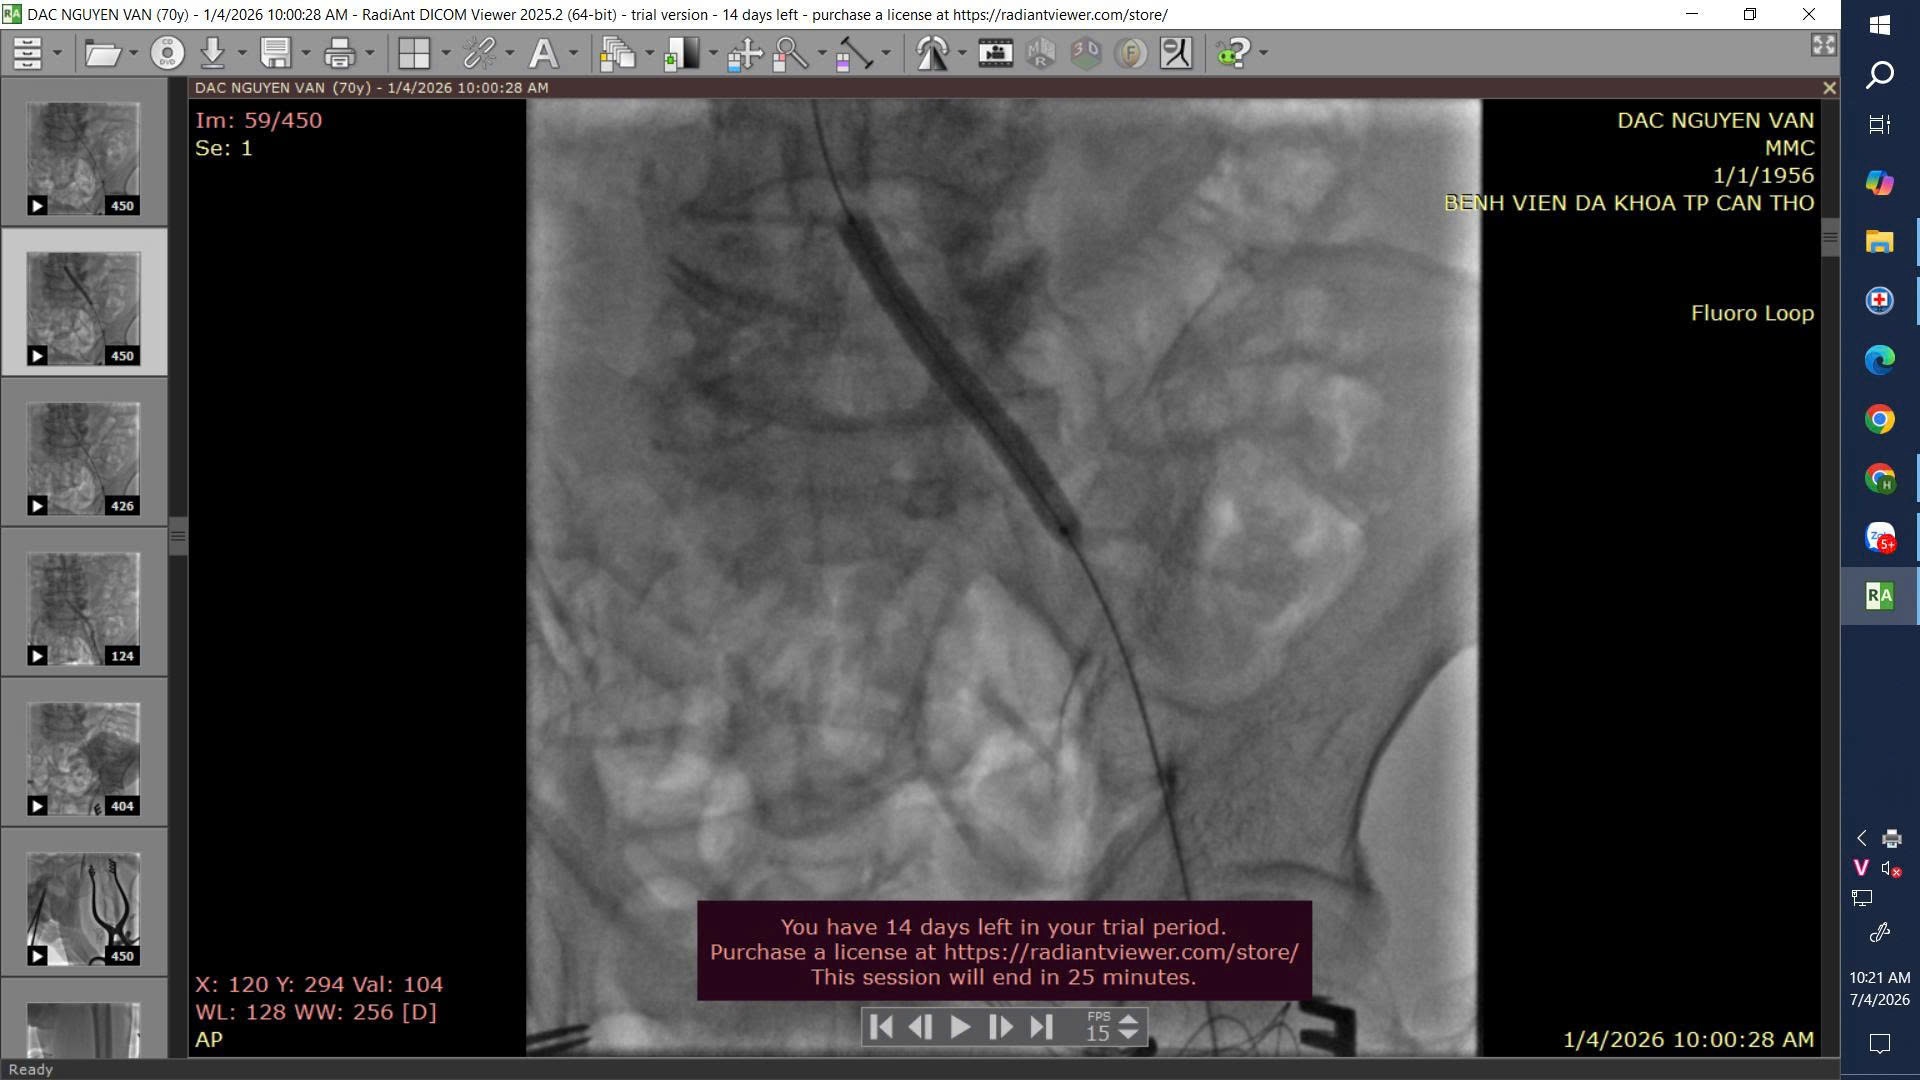

Trước tình trạng tổn thương phức tạp, ê-kíp Khoa Ngoại Lồng ngực đã tiến hành can thiệp nội mạch, nong bóng và đặt stent tại động mạch chậu trái, đồng thời tái thông động mạch đùi nông. Ca can thiệp diễn ra thành công, giúp khôi phục lưu thông máu cho chi dưới.